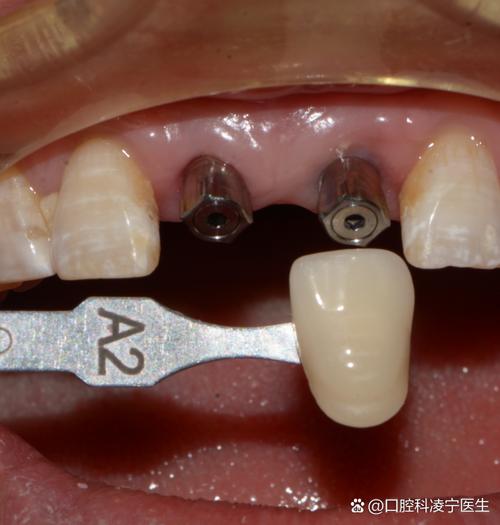

- 主要方法: 外科手术将人工牙根(种植体)植入牙槽骨,待骨结合后安装基台和牙冠。

- 特点: 目前公认的最佳修复方式之一,不损伤邻牙,功能、美观、稳定性最好,但费用最高,治疗周期较长(通常3-6个月),对全身健康和口腔条件有一定要求。